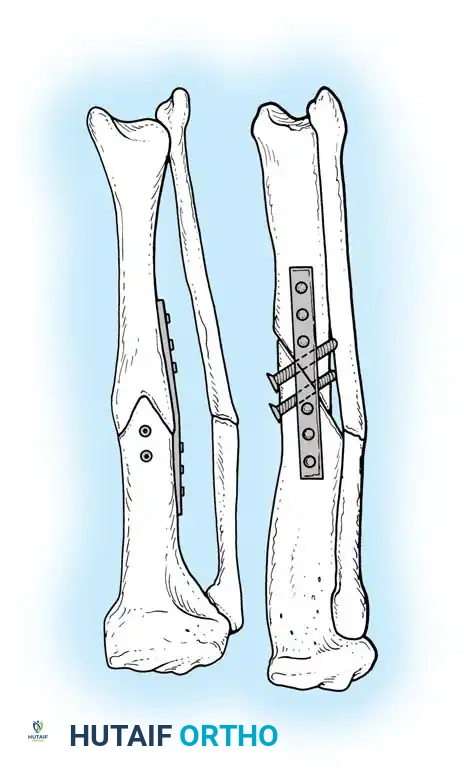

Plate and Screw Fixation

Oblique tibial osteotomies stabilized with dynamic compression plates and lag screws provide rigid fixation and allow for precise correction of multiplanar deformities. E.E. Johnson and Sanders et al. have demonstrated excellent functional results using this technique, achieving simultaneous correction of angulation, rotation, and length.

Fig. 5: Application of a dynamic compression plate following an oblique osteotomy.

- Definitive Fixation: Apply a broad dynamic compression plate (or locking plate) to the tension side of the deformity. Secure the osteotomy with interfragmentary lag screws placed through the plate or independently outside the plate to maximize compression across the broad osteotomy surface.

- Grafting: If a significant gap exists or if lengthening exceeds 1.5 cm, pack the defect with autogenous cancellous bone graft.